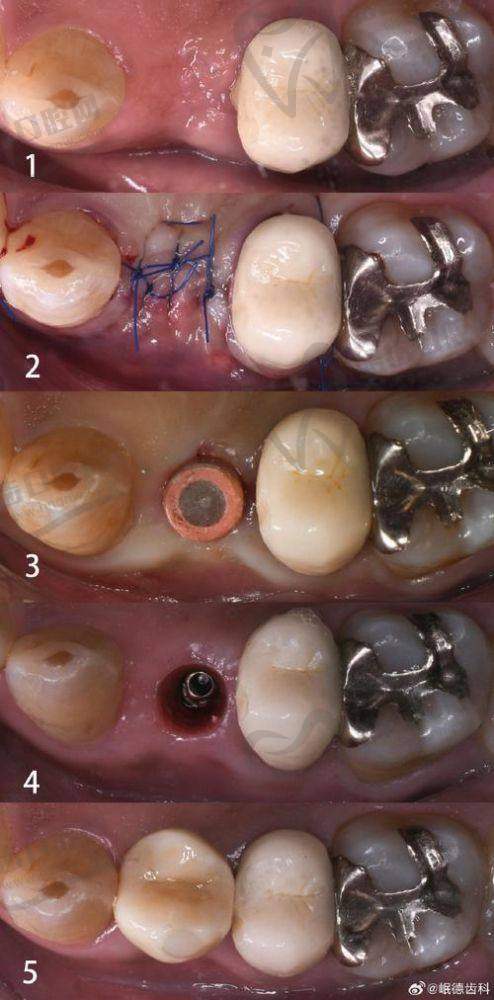

周毅医生在种植牙领域有着极高的造诣。他是口腔种植和口腔修复两个首批国内临床重点专科的骨干成员,在医院先开展了穿颧种植等一系列高难度手术和治疗项目,折断种植体螺丝取出技术处于国内外领跑地位。

他凭借丰富的临床经验和不错的技术,能够根据患者的具体情况制定个性化的种植方案,确保种植成效的美观和功能的修复。同时,他注重手术的安心性和舒适性,尽可能减少患者的痛苦。许多患者在接受周毅医生的种植牙手术后,都对成效非常满意,称赞他的技术高超、服务贴心。